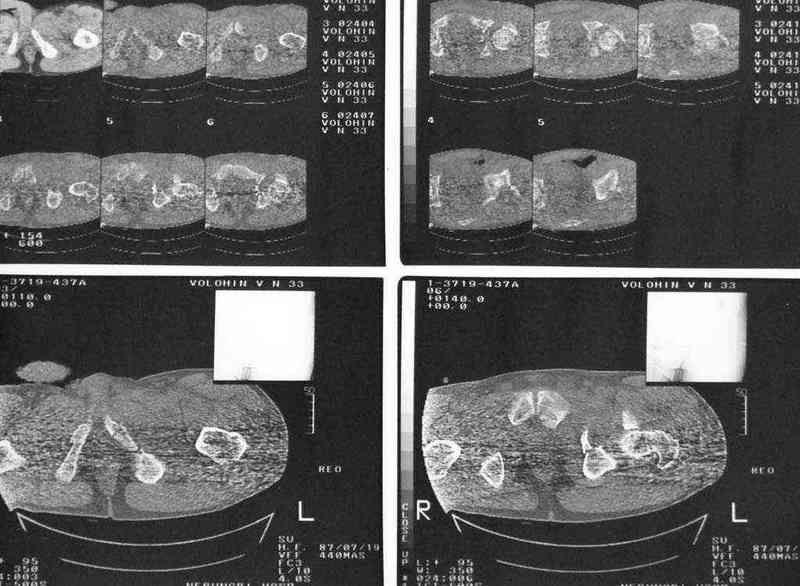

Дополнение, минимальный набор необходимых прекций, необходимых для лечения повреждений вертлужной впадины

Фас. Inlet

Подвздошная Запирательная